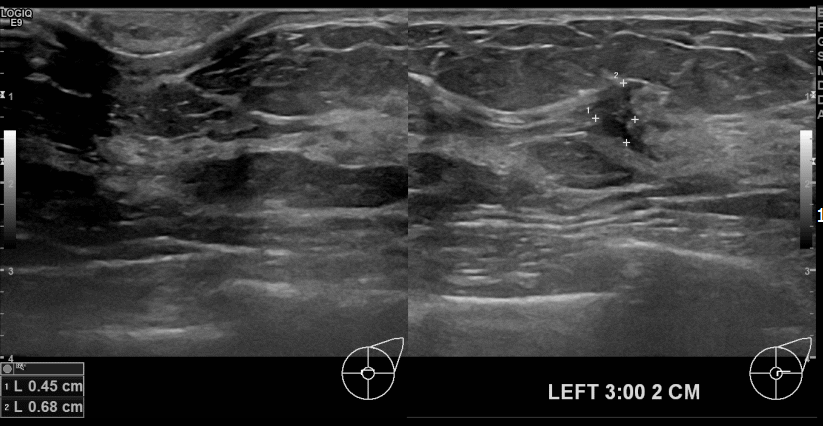

아산유외과개원후 694번째 유방암진단

상기환자 건진상 이상소견으로내원하신 40대 여성분으로 좌측유방멍울 조직검사시행후 유방암 진단되었습니다